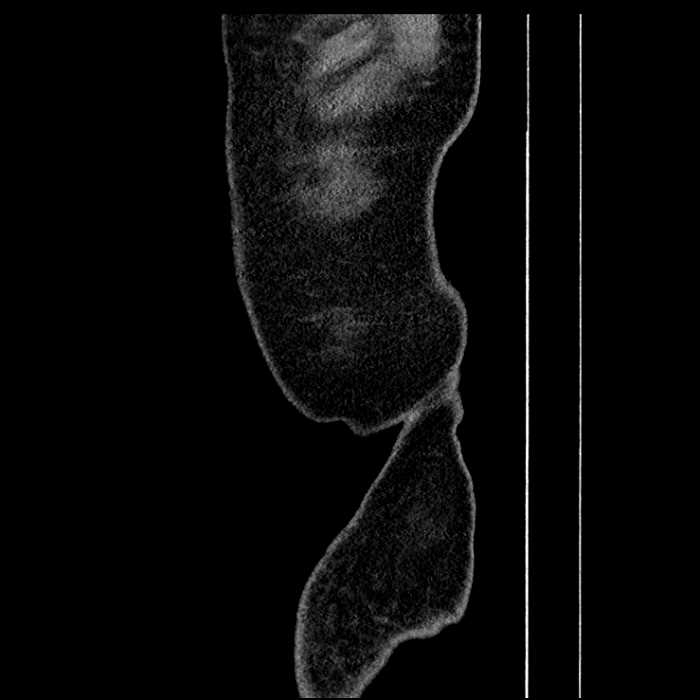

• High grade stenosis of the left common iliac artery, with the left internal and external iliac arteries remaining patent

High grade stenosis of the left common iliac artery. The left external and internal iliac arteries are patent.